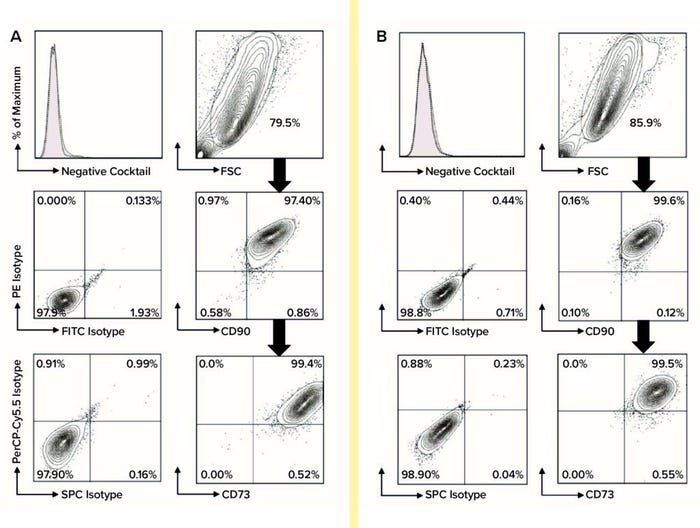

Using flow-cytometric analysis of six biological replicates, we assessed cells from each extraction and culture condition for expression of MSC biomarkers (CD44, CD73, CD90, and CD105) and for nonexpression of hematopoietic lineage cell markers (CD45, CD34, CD11b, CD19, and HLA-DR). We used FlowJo software from Tree Star for post-acquisition analysis (Figure 2). Using the gated percentages of double-positive CD90-FITC and CD44-PE biomarkers multiplied by double-positive CD105-PerCP-Cy5.5 and CD73-APC biomarkers (percentages from FlowJo), we calculated the quadruple-positive MSC percentages of each sample for all conditions at P2 and P7. Subsequently, to determine the purity of MSCs in each set of conditions at P2 and P7, we calculated the mean and SD of quadruple-positive MSC percentages for each.

Figure 2: For flow-cytometric analysis of MSCs at passage 7, cells were stained using anti-CD73-APC, anti-CD90-FITC, and anti-CD105- PerCP-Cy5.5 along with relevant isotype controls using a Stemflow hMSCs analysis kit from BD Bioscience. Markers associated with hematopoietic lineage cells also were stained using a negative cocktail of PE-conjugated antibodies specific for CD45, CD34, CD11b, CD19, and HLA-DR. Controls are represented by the left column in each category, with MSC surface-marker expression in each right column. MSCs were gated in the FSC-SSC plot and subgated to reveal expression levels of CD44, CD73, CD90, and CD105; subgate cells mostly appear in the top-right quadrant of the plot, indicating positive biomarker expression. A total of six biological replicates were analyzed for each condition: (A) flow-cytometric analysis of DMEM:F12–cultured MSCs and (B) flow-cytometric analysis of PTT-6–cultured MSCs.

Based on standards recommended by the International Society for Cell and Gene Therapy (ISCT), MSC purity is defined by positive expression of a group of specific surface markers —CD44, CD73, CD90, and CD105 — and a lack of expression for hematopoietic stem cell (HSC) surface markers CD34, CD45, CD11b, CD19, and HLA-DR. Decreasing expression levels of MSC-specific surface markers implies a cell purity reduction. So we compared the purity of MSCs cultured in different conditions across passages by examining the expression levels of MSC-specific markers (Figure 4, right). Tabulated flow-cytometry results revealed that PTT-6–cultured cells maintained persistent high purity across multiple passages (98.4 ± 1.9% at P2, 99.1 ± 1.1% at P7), whereas DMEM:F12–cultured cells expressed marginally lower levels of those markers at P2 (95.8 ± 2.5%) that increased by P7 (96.8 ± 3.3%).

When we compared tissue sources and extraction methods, we found no observable differences in MSC purity (data not shown), which indicates that it is medium dependent. No cultured cells expressed HSC surface markers. PTT-6–cultured cells demonstrated significantly higher surface-marker expression than did DMEM:F12–cultured cells (p < 0.05) at both P2 and P7 (Figure 4, right). On comparing the median fluorescence intensity (MFI) of individual MSC biomarkers from P2 and P7 (Figure 5), we found increased CD73 expression in DMEM:F12 cultured cells and an increase in the expression of CD90 in PTT-6–cultured cells.